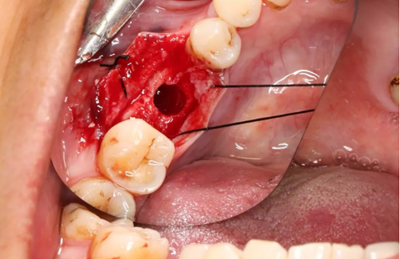

12、延期種植手術(shù)過(guò)程

使用直徑3mm的環(huán)形取骨鉆切取長(zhǎng)約9mm的柱狀骨標(biāo)本,用于組織學(xué)和顯微影像檢查

由于取骨致窩洞較大,加之缺牙間隙大,只好選擇植入5mm直徑種植體;種植備洞完成后,頰側(cè)骨壁厚度僅約1mm。

(攝于2017年4月14日)

植入國(guó)產(chǎn)威高(WEGO)5.0×11mm種植體,檢查種植體位于理想軸位。